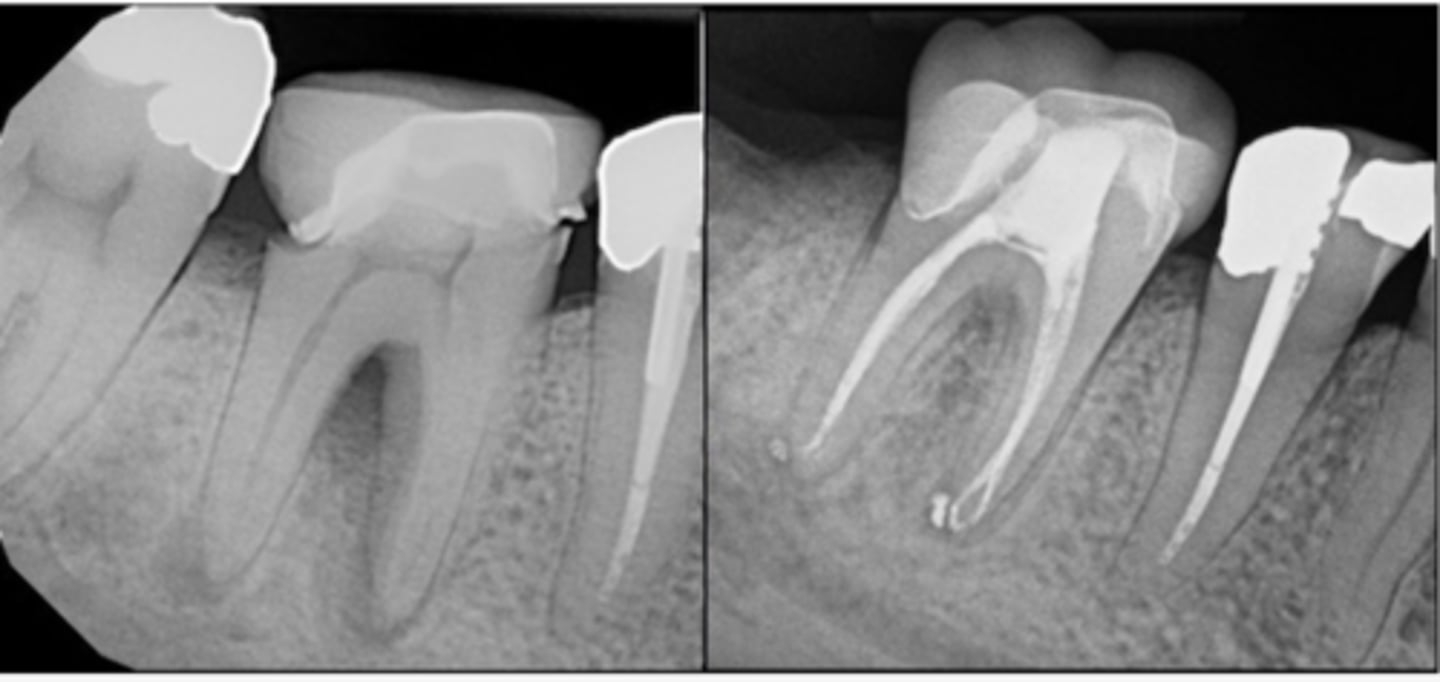

What type of lesion?

Furcation involvement and loss of buccal plate extending apically on tooth #19, visible in CBCT rendering (left) and pre-op PA radiograph (center)

Endodontic treatment was initiated and calcium hydroxide medication was placed

Four months later, tooth was obturated and healing of furcal bone was evident radiographically (right)

Primary endo with secondary perio lesions